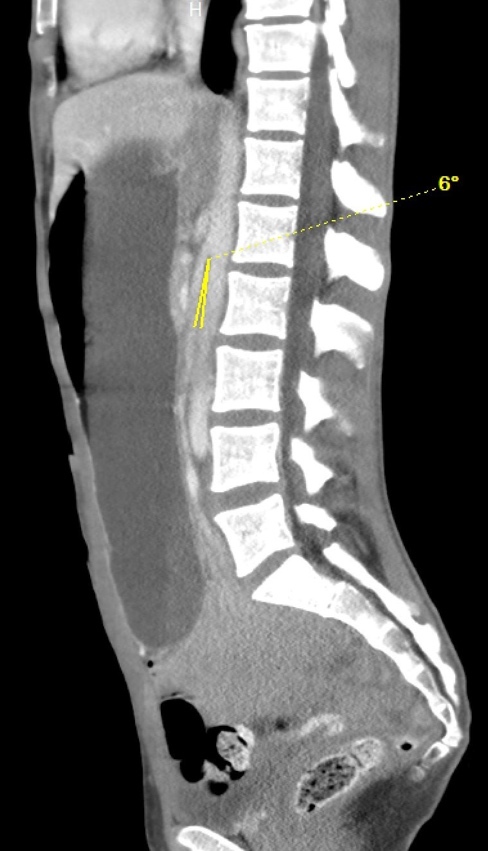

On hospital Day 1, an esophagogastroduodenoscopy (EGD) with nasogastric tube placement was completed with removal of approximately two liters of chyme (i.e., acidic gastric fluid). Initial computer tomography was reviewed by Radiology, and SMAS was diagnosed (Images 1 and 2). After a multidisciplinary review consisting of the case’s internal medicine, gastroenterology and general surgery teams, the patient was transferred to a tertiary care center where a gastrostomy-jejunostomy tube was placed. She was started on tube feedings and reported improvement of symptoms at follow-up one month later.

Pertinent findings on physical exam included mid-epigastric abdominal pain with an underweight BMI of 18.6. Computer tomography of the abdomen and pelvis with intravenous contrast provided a radiological diagnosis of SMAS (Images 3 and 4).